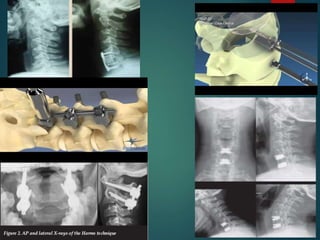

 Tecnica Gallie

 Tecnica Brooks